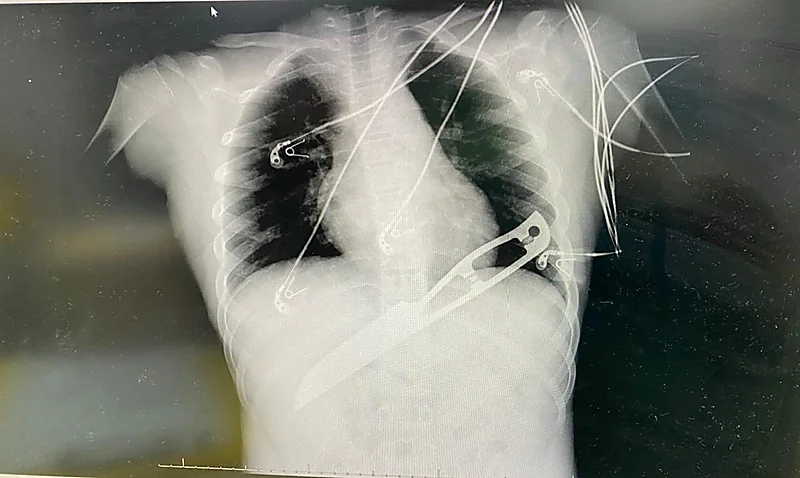

وأوضح الإستشاري المناوب / فرخ عالم بقسم الجراحة بمستشفى حراء أن الطفل وفور وصوله إلى قسم الطوارئ تم استدعاء فريق الجراحة العامة المناوب لتقييم الحالة حيث أفاد بأن مثل هذه الحالات تعتبر بالغة الخطورة ، إذ أنه وأثناء إجراء عمليات مماثلة قد يحدث نزيف حاد عند نزع السكين من المريض ، وفي نفس الوقت لابد من إزالتها رغم خطورة العملية على حياة الطفل ، حيث كانت حالة الطفل غير مستقرة وعلى أثره تم البدء في الإسعافات الأولية من المحاليل وكذلك تجهيز وحدات الدم لتعويض النزيف المحتمل أثناء العملية وتم عمل تصوير الأشعة السينية والسونار ، وعليه تقرر نقل الطفل إلى غرفة العمليات على وجه السرعة بعد شرح العملية و كافة مضاعفاتها من قبل الفريق الطبي لذوي الطفل .